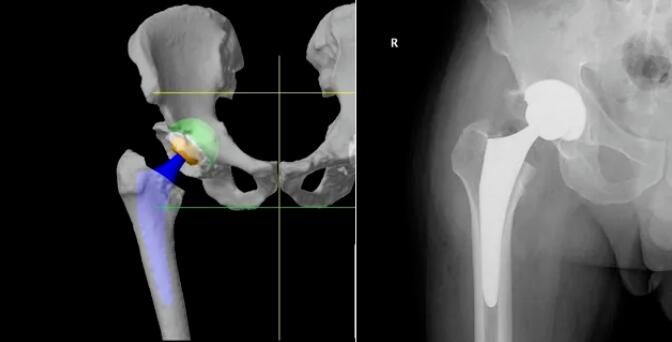

利用患者术前CT数据构建3D骨骼模型,通过导航模块在专属3D模型图像上规划植入物尺寸与摆放位置,对安装效果和截骨量、截骨角度等进行提前“预演”,实现精准术前方案定制。

借助限制性立体定位边界与三维可视化截骨界面,独有的反馈式机器臂辅助医生实现精准截骨与假体精准安放。患者不仅恢复更快、使用体验更佳,同时有效降低磨损率与并发症,延长假体使用寿命,让“一次置换用终生”成为可能!

相较于传统关节置换手术依赖医生个人经验、存在假体定位欠佳与术后并发症风险等问题,Mako智能手术机器人辅助置换,为医生的操作精准度和患者的术后恢复带来了突破性进步。从“经验主导”到“智能精准”,每一台手术都以严苛标准执行,大幅降低手术风险,缩短康复周期。